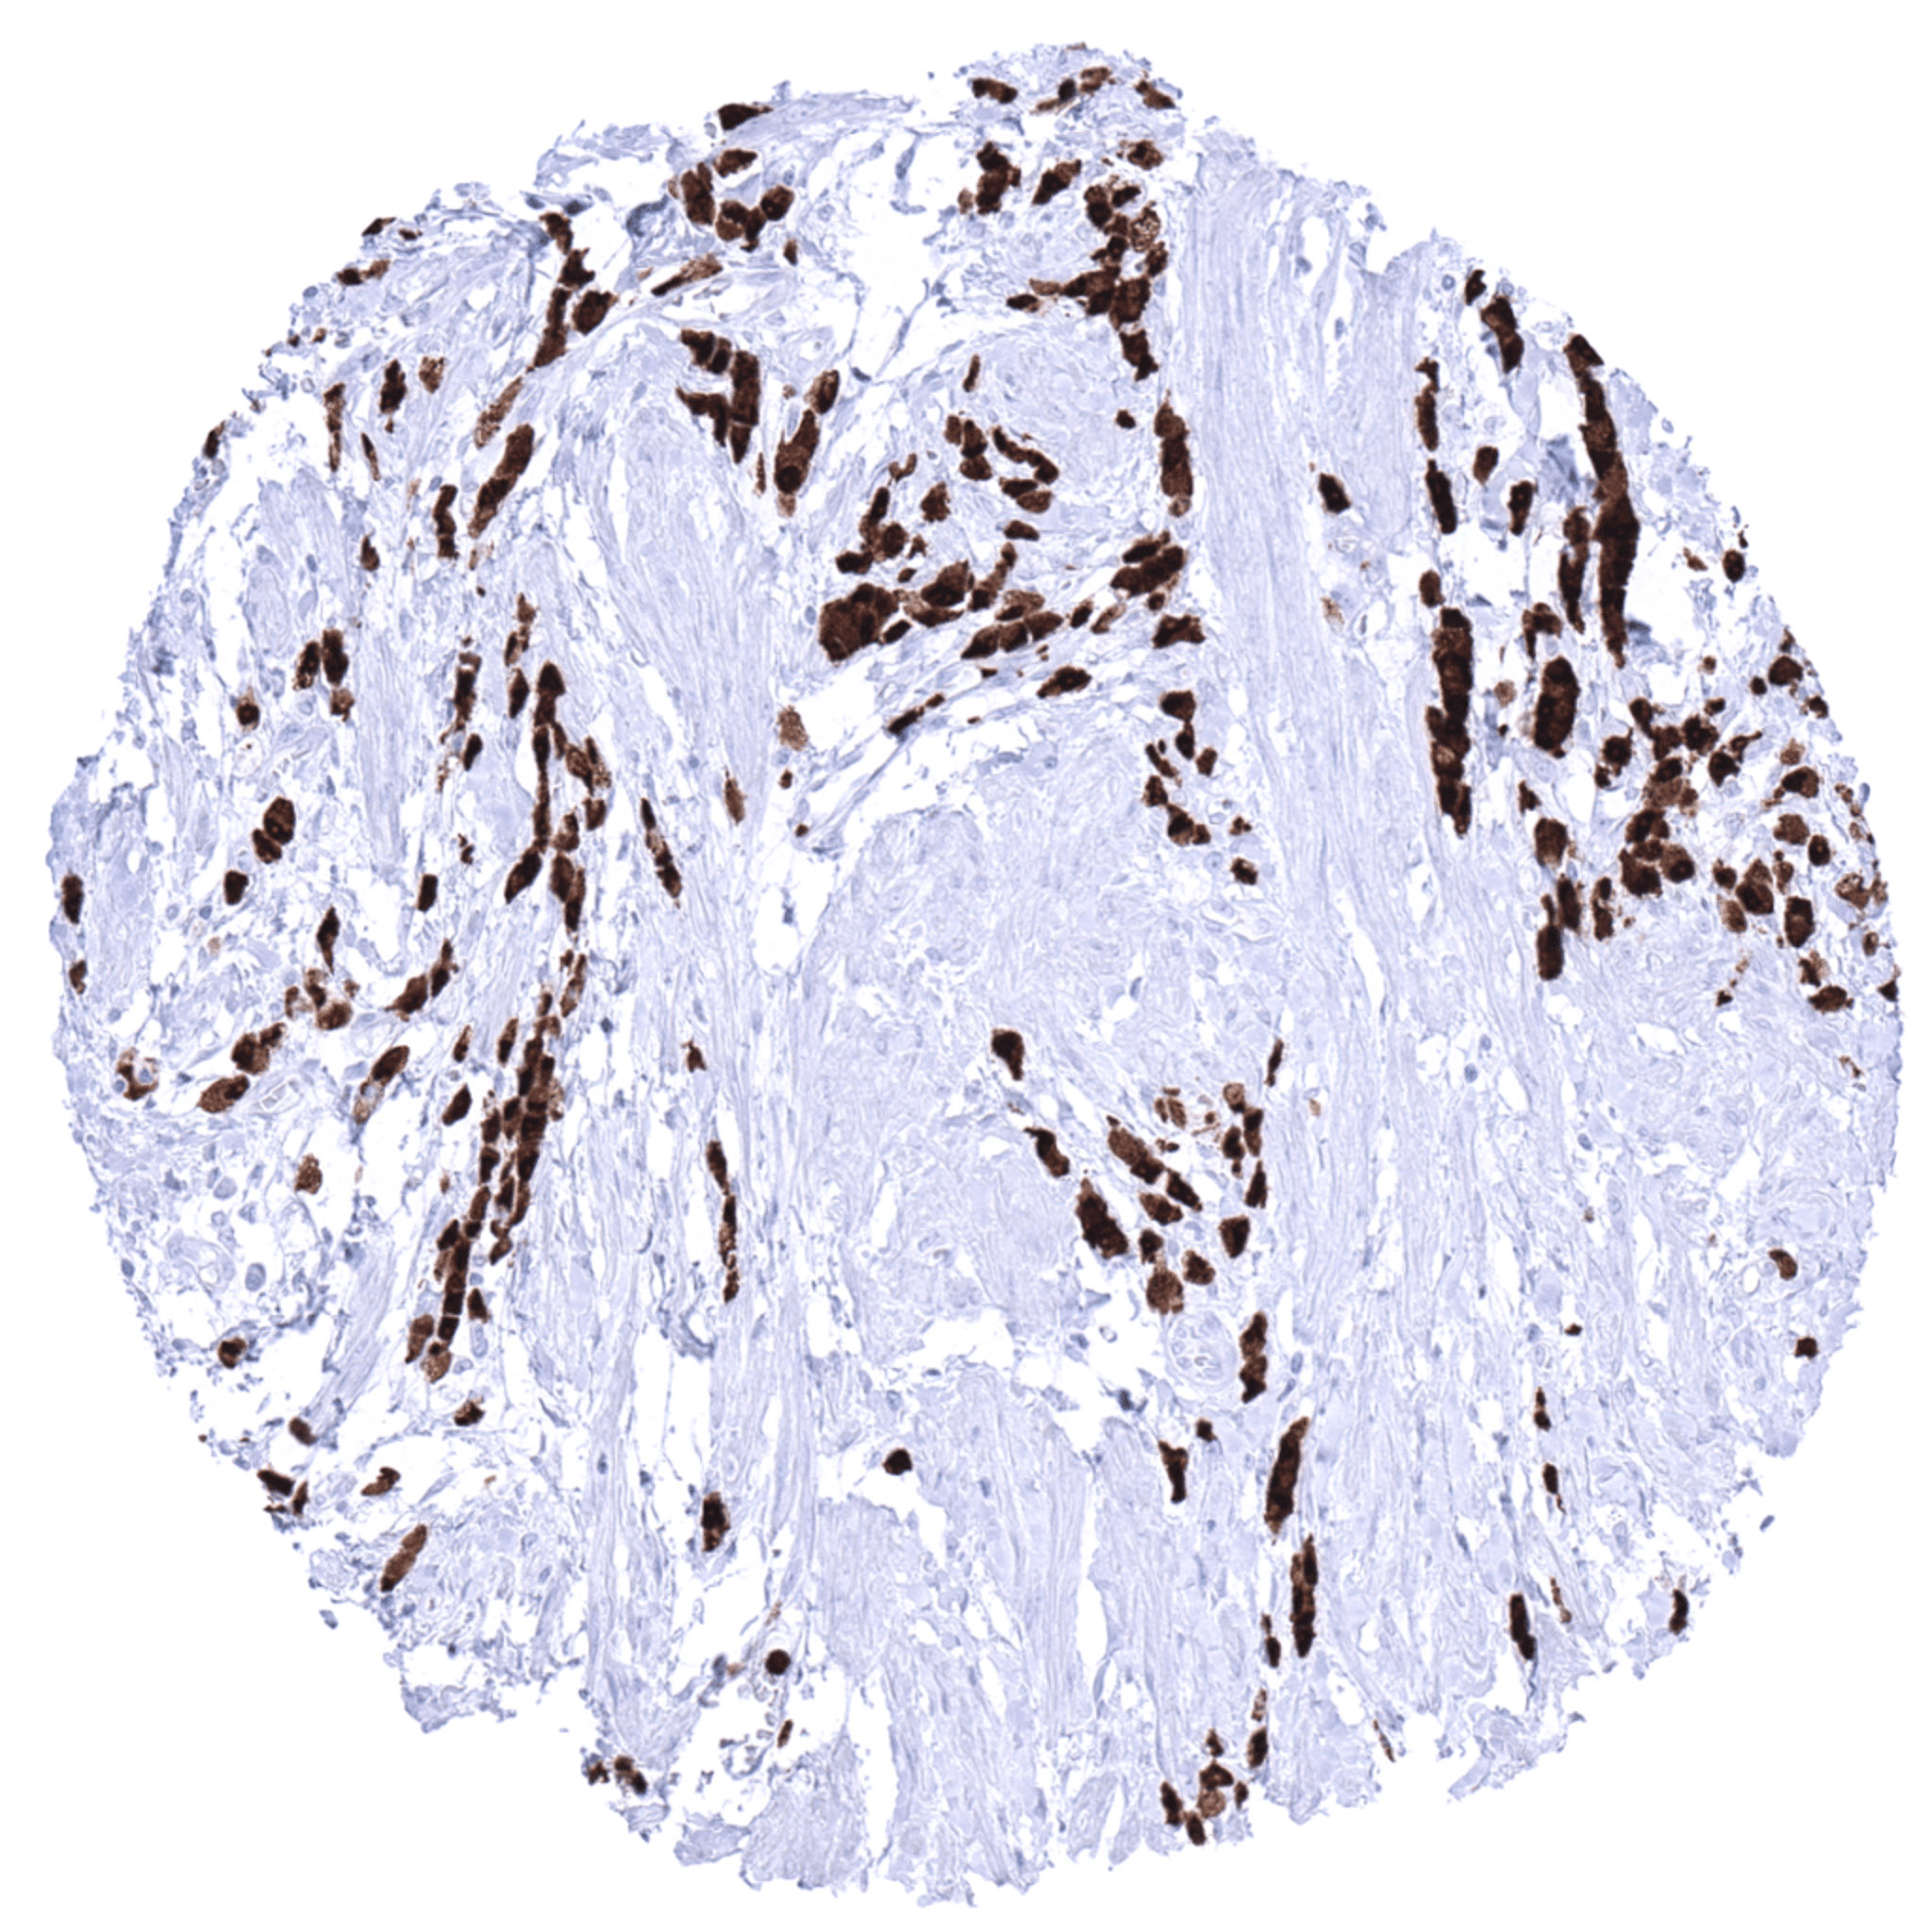

Lymph node- S100P negative Hodgkin’s lymphoma containing numerous S100P positive granulocytes.